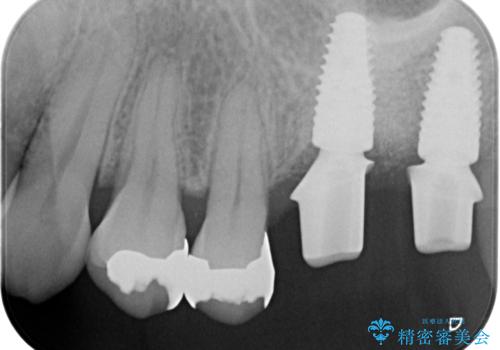

上顎奥歯のインプラント治療

- 奥歯を失い咬合機能の回復のためインプラント治療を希望され来院されました。

奥歯を2本失うと、他の歯の負担が増加し残っている歯の状態が悪くなるリスクがあります。

しっかりと咬合機能の回復できるインプラント治療を計画します。